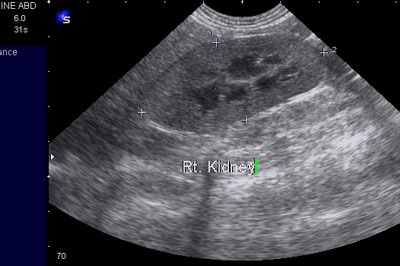

We have a complement of 4 scopes for medical and diagnostic procedures. Imaging – X-rays and contrast radiology are important diagnostic tools. We use both a standard X-ray machine and a dental-specific X-ray machine. The addition of a new Siemens G50 color Doppler ultrasound unit greatly complements and enhances the imaging of tissues, heart and abdominal organs.

The Ultrasound unit is part of the imagery equipment, and is used to detect many soft tissue anomalies. We

use ultrasound to examine abdominal structures, perform pregnancy diagnostics, examine your pet's cardiac function and check for certain diseases in the eye.